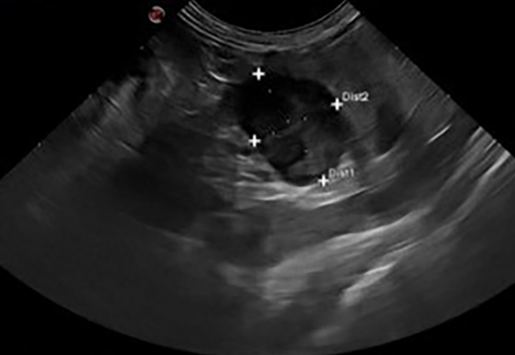

고양이 갈색 세포종

고양이 부신의 종양성 변화는 매우 드문 질환에 해당한다.

그 이유가 고양이는 원래 adenoma 계열의 분비샘류의 종양이 잘 발생하지 않기 때문이다.

하지만 그렇다고 전혀 발생하지 않는것은 아니기 때문에 간혹 이런 케이스 논문이 나온다.